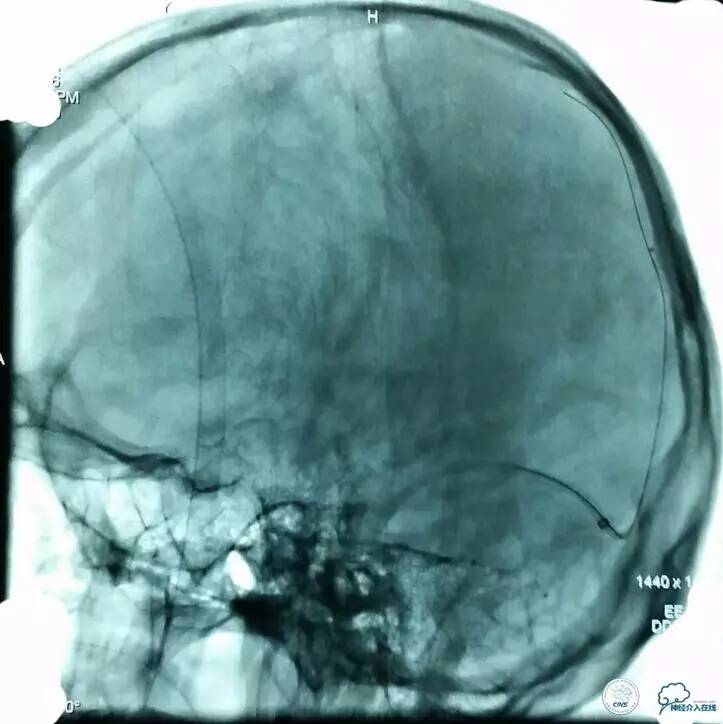

▼正位造影:

▼正位: